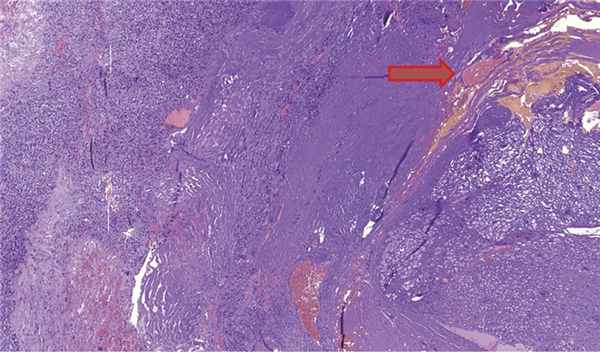

Гистологическая характеристика опухоли

Гистологическое исследование (рис. 4) подтвердило микроскопический диагноз гемангиобластомы. Опухоль построена из двух типов клеток: стромальные клетки с оптически пустой цитоплазмой и большое количество сосудистых клеток. Опухоль окружена тонким слоем фиброзной ткани, к которой тесно прилежат фрагменты нервной ткани и скопления ганглиозных клеток (рис. 5).

Рис. 4. Гемангиобластома. Стромальные клетки с оптически пустой цитоплазмой (указано красной стрелкой) и сосудистые клетки (указано синей стрелкой). Окраска гематоксилином и эозином, ув. ×200. Рис. 5. Гемангиобластома (указано красной стрелкой) и скопления ганглиозных клеток (указано зеленой стрелкой). Окраска гематоксилином и эозином, ув. ×100.

Во время исследования был обнаружен прилежащий нервный стволик (рис. 6), такую же находку описывают R. Pluta и соавт. [2].

Рис. 6. Гемангиобластома и прилежащий нервный стволик (указан стрелкой), Окраска гематоксилином и эозином, ув. ×50.